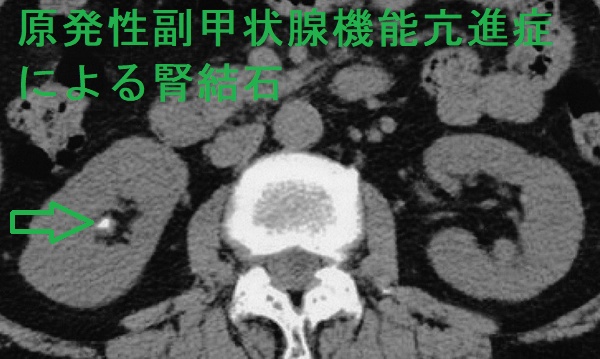

- 過剰な血清カルシウムが腎結石(腎臓結石)・尿路結石を形成し腎不全

原発性副甲状腺機能亢進症の約4%に、高カルシウム血症による腎結石(腎臓結石): 内分泌尿路結石を認めます[Urolithiasis. 2018 Oct;46(5):453-457.][J Clin Endocrinol Metab. 2011 Aug;96(8):2377-85.]。

原発性副甲状腺機能亢進症の腎結石(腎臓結石): 内分泌尿路結石はリン酸カルシウム結石です。[JAMA Surg. 2020 Sep 1;155(9):861-868.]